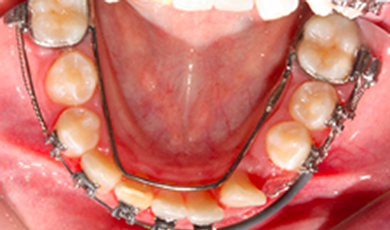

Início do tracionamento

Inicio do tracionamento ortodontico apos exposicao cirurgica ainda com a presenca de dentes deciduos, utilizando um arco lingual de apoio.